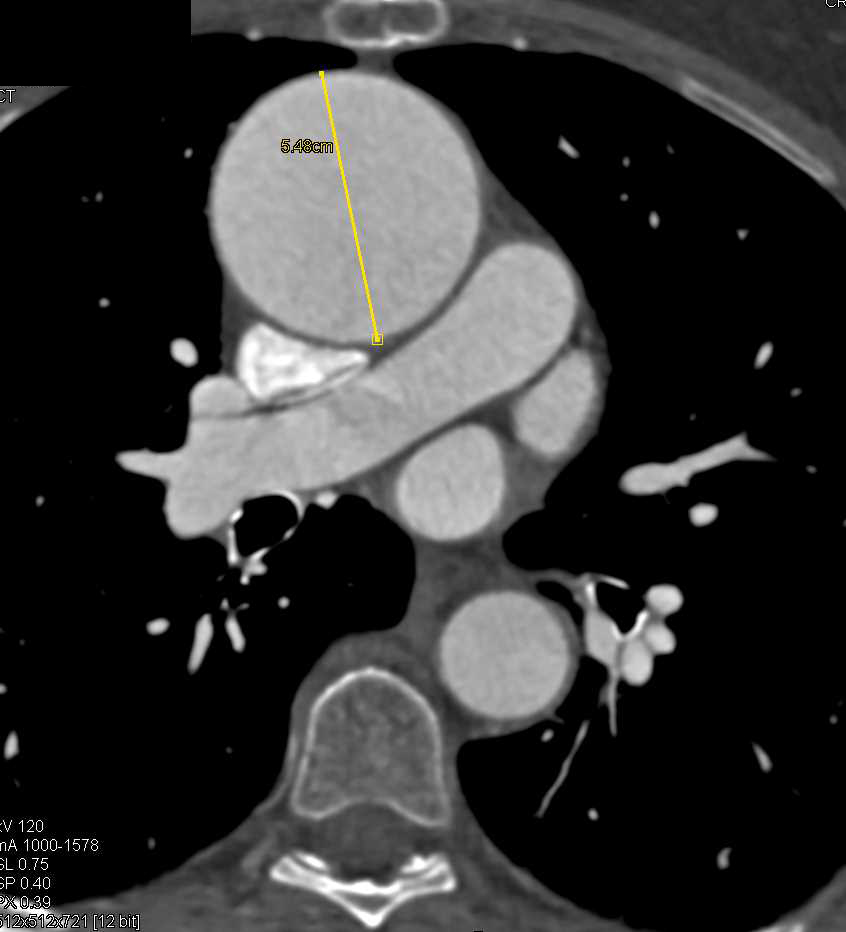

Pseudoaneurysm of the Aortic Root Following Aortic Valve Replacement (AVR)